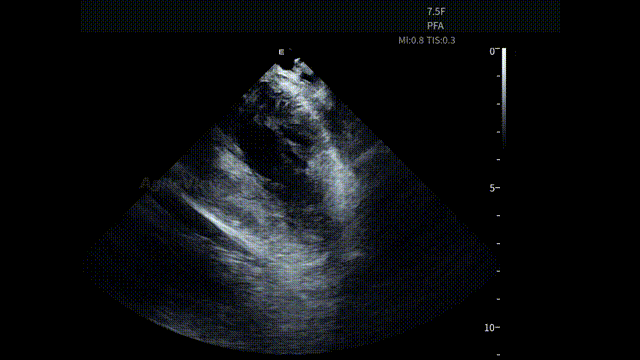

▶【房间隔穿刺与左房进入:路径清晰,节奏连贯】

在全球最细 7.5Fr ICE的持续影像引导下,术者完成房间隔穿刺。AgileView™ ICE实时显示房间隔 tenting及穿刺针跨隔过程,使穿刺路径和深度判断更加明确。穿刺成功后,PulseSelect™导管顺利进入左心房,整体操作节奏紧凑。

在另一台孙奇教授主刀的AgileView ™ ICE 结合冷冻球囊消融的手术中, ICE 也为后续 冷冻球囊导管跨间隔进入左房及空间定位提供影像支持,整体操作节奏紧凑、路径清晰。

房间隔穿刺(PulseSelect™手术)

房间隔穿刺(AFA冷冻消融手术)